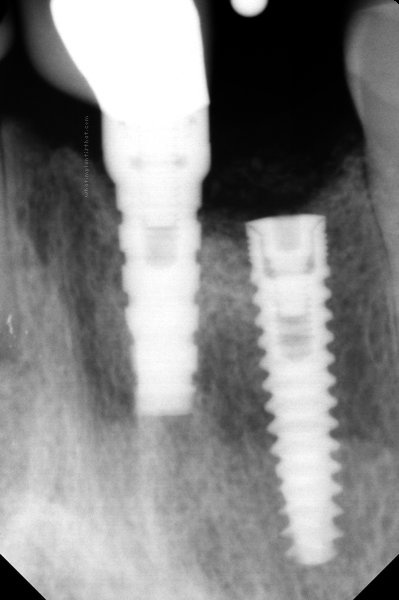

Sybron [Innova]

Sybron Anatomic

Connection Interface

Internal interface

Body Shape

Tapered body

Thread Design

ThreadedSquare threads

Additional Features

Straight flangeCollarFlat apex